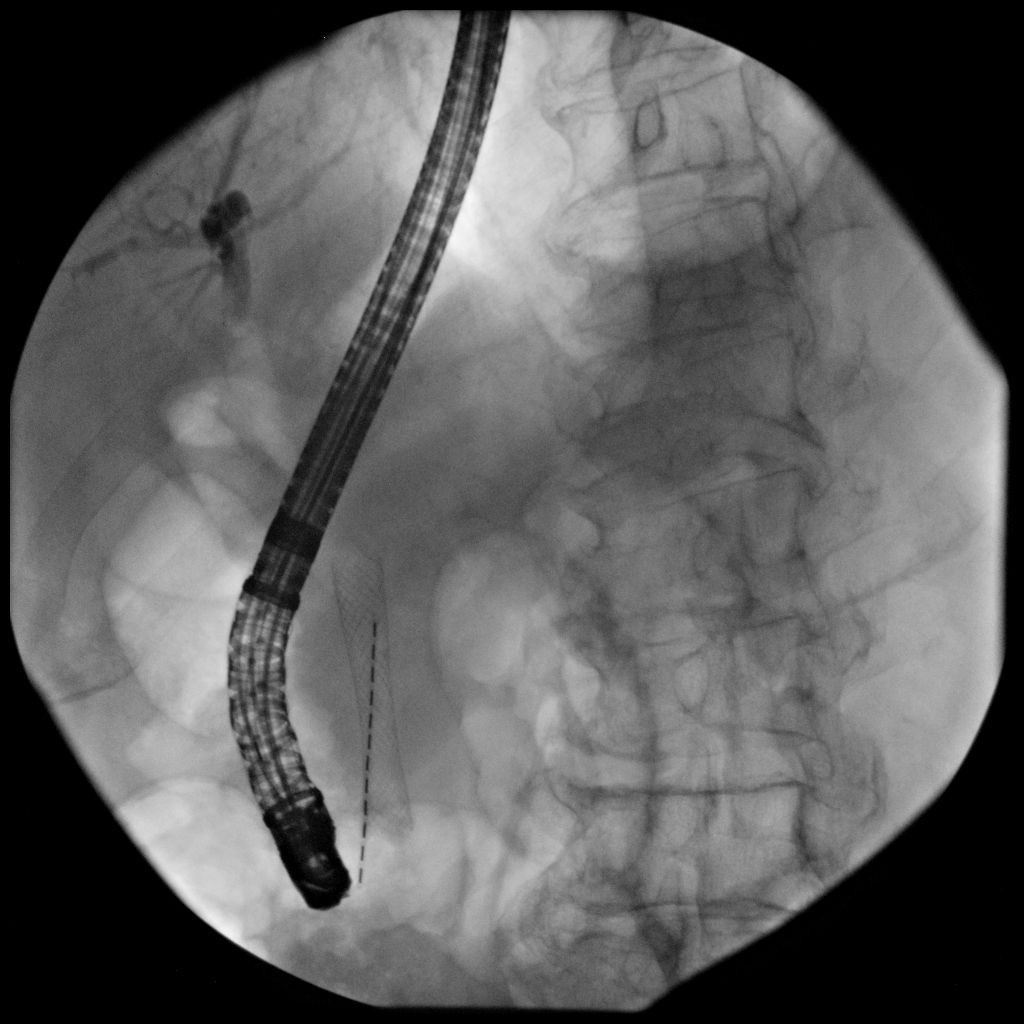

对于高龄患者,或已经有转移的,无法进行手术治疗的患者,经内镜逆行胰胆管造影术(ERCP)放置胆道支架,解除胆道梗阻,减黄治疗是主要的方法,可明显延长生存期,提高生活质量,均优于外科手术。同时也可以手术中放置胰管支架,对胰腺癌后期疼痛缓解有非常明显的作用。

支架可以放置金属支架或塑料支架,可以快速减黄,提高生活质量、延长生存期。

(图1:造影下放置胆总管金属支架。图2:内镜下放置胆总管金属支架。图3:同时放置胆道塑料支架和胰管支架。图4:放置金属支架同时放置放射粒子支架局部放疗)